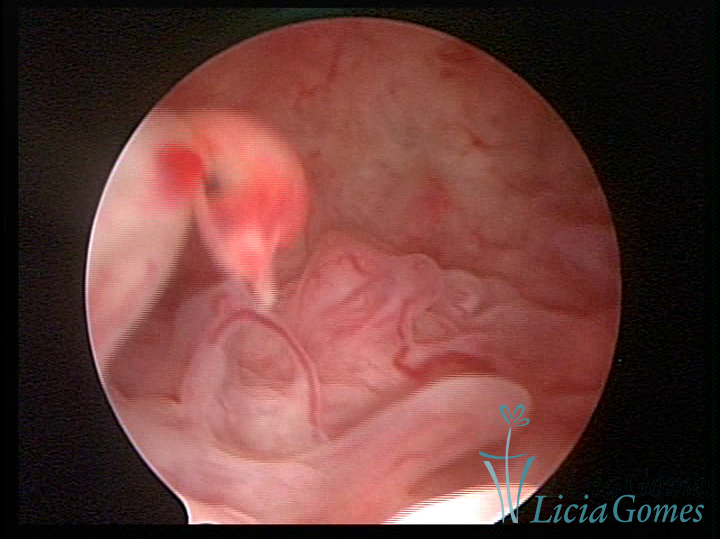

Mas poderá verificar se as lesões são do tipo: focal; regional ou difusa

Este pode apresentar uma gama variável de aspectos macroscópicos, com aspecto pseudopolipoide; lembrando tecido cerebroide ou com reação deciduoide;a vascularização superficial é mais evidente e com vasos em formatos de saca-rolha ou espirais visualizando também a vascularização com atípias, com aumento do calibre dos vasos superficiais, pode ser encontrado também tecido em necrose, poderá haver um pequenos dendritos (papilomatoso).